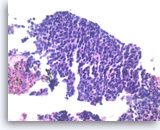

Acinar cell carcinoma,

Pancreas FNA, Cell Block.

The tumor cells form a prominent cribriform growth pattern with a deceptively bland and uniform appearance. A prominent cribriform pattern would be unusual for a low grade neuroendocrine neoplasm but immunohistochemistry is required to make the distinction. (Courtesy of Dr. Andrew Fischer)

10X

Acinar cell carcinoma,

Pancreas FNA, Cell Block.

The tumor cells form a prominent cribriform growth pattern with a deceptively bland and uniform appearance. A prominent cribriform pattern would be unusual for a low grade neuroendocrine neoplasm but immunohistochemistry is required to make the distinction. (Courtesy of Dr. Andrew Fischer)

10X